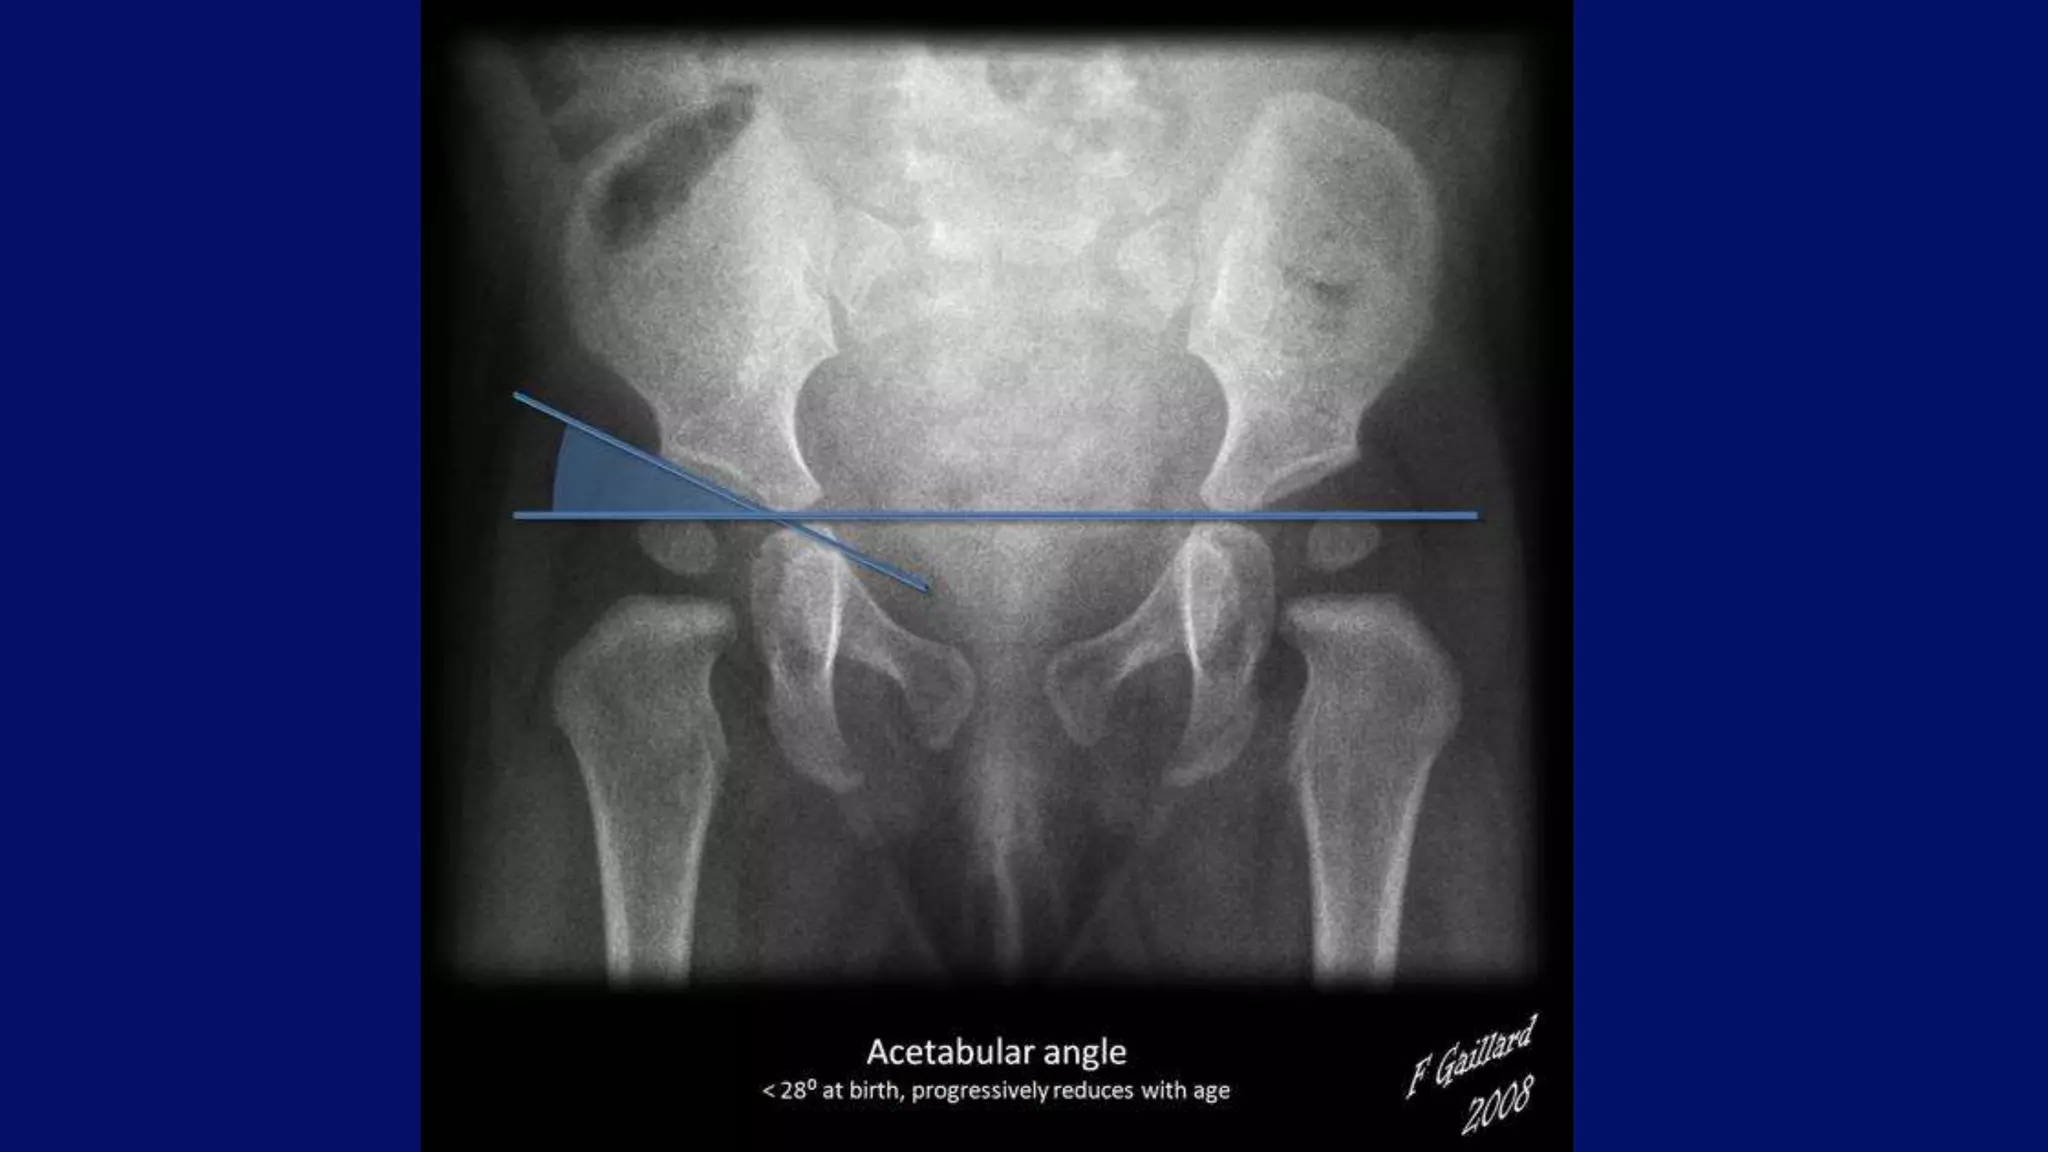

•Putti's triad for developmental dysplasia of the

hip include :

Superolateral displacement of proximal femur .

Increase in acetabular angle.

Small capital femoral epiphysis.

Developmental dysplasia of the hip

• #68 36 degree acetabular angle.